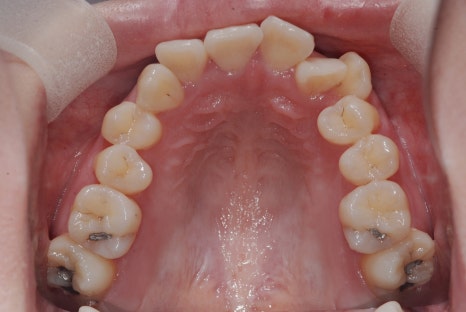

< 스마일디 치과 비발치 before & after >

*치료 전후 사진은 환자의 동의하에 게재하였으며, 동일한 환경과 조건에서 촬영된 전후 사진입니다.

악궁 확장

좁아져 있는 치아들의 아치(악궁)를 환자 본래의 이상적인 크기로 넓혀주어,

삐뚤어진 치아들이 배열될 공간을 만들어냅니다.